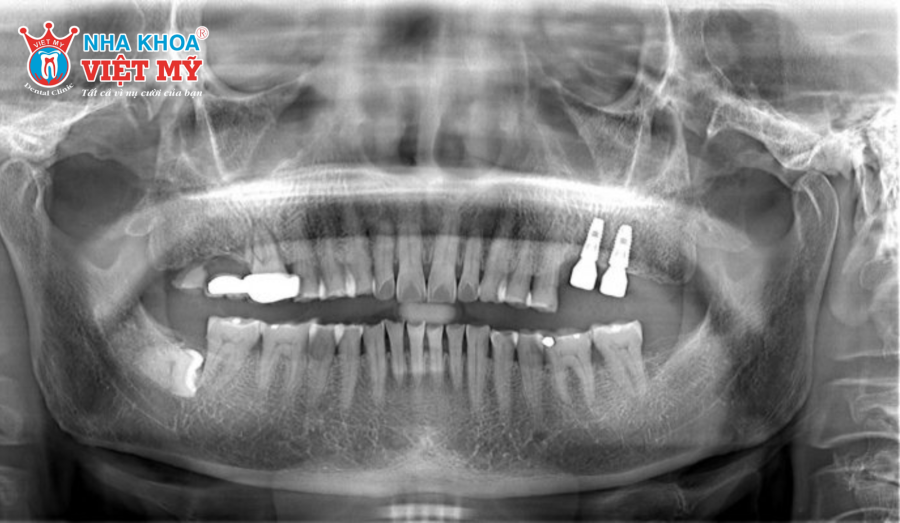

- Tình trạng xương hàm và chất lượng xương tại vị trí nhổ răng: Nếu xương hàm còn đủ độ dày và cứng, trồng Implant sẽ dễ dàng hơn và có thể rút ngắn thời gian điều trị. Ngược lại, nếu xương đã mất nhiều, bác sĩ cần thực hiện ghép xương trước khi đặt trụ để tăng độ tích hợp.